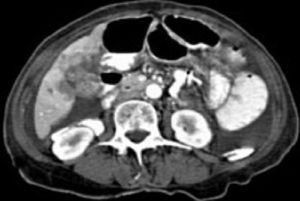

Gall bladder cancer is very rare even though it is very lethal. Adenocarcinoma is the most common type. Occurs late in life, having gall stones is a risk factor for developing cancer. Chronic salmonella typhi is also a risk factor. Evaluation is by US / CT. Treatment is palliative stenting of bile ducts or surgical resection for palliation only. Almost all patients die within one year.